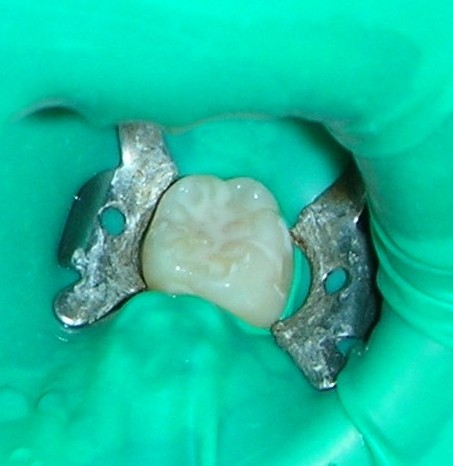

由於牙齒發育的關係,不論是乳牙的臼齒或恆牙的小臼齒及大臼齒的咬合面都滿佈著又細又深的溝隙(圖1),連最細的牙刷毛,尺寸都比溝隙大很多,更本無法深入其中清潔(圖2),但是蛀牙菌的尺寸非常小,所以輕易就能定居其內,而這些天生的”缺陷”,又經常”陷住”食物殘屑,持續的供應養分給蛀牙菌。如此容易藏汙納垢,卻又難於清潔,所以成為牙齒最容易發生蛀牙的地方。

1. 將牙齒用橡皮布或棉捲隔離---這個步驟很重要,因為在塗佈過程中能防止牙面被唾液污染,使封填劑黏附的更緊密,防蛀效果更佳,效期更長。